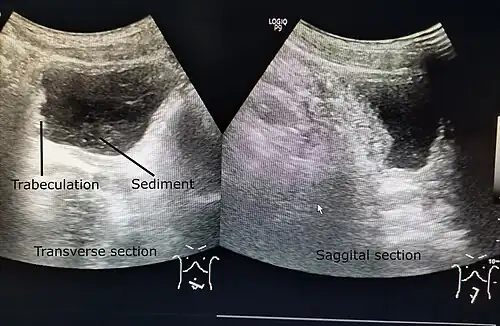

| A paraplegic patient with neurogenic bladder on regular ultrasound follow-up showing thickened bladder wall with trabeculations and sediments within the bladder. | |

Ultrasound imaging can give information on the shape of the bladder, post-void residual volume, and evidence of kidney damage such as kidney size, thickness or ureteral dilation.[12] Trabeculated bladder on ultrasound indicates high risk of developing urinary tract abnormalities such as hydronephrosis and stones.[13] A voiding cystourethrography study uses contrast dye to obtain images of the bladder both when it is full and after urination which can show changes in bladder shape consistent with neurogenic bladder.[12]